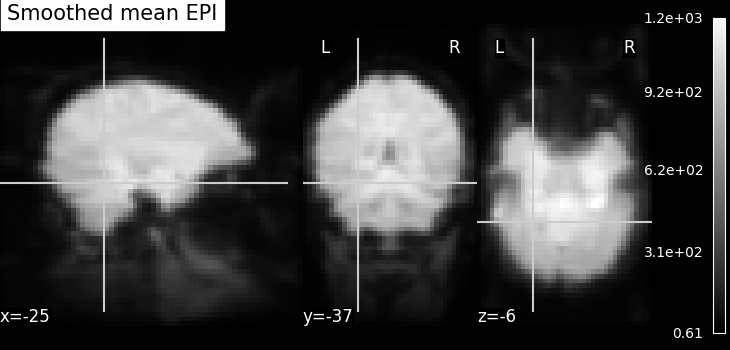

We have the datasets in hand especially paths to the locations. Now, we do simple pre-processing step called as image smoothing on functional images and then build a statistical test on smoothed images.

Smoothing: Functional MRI data have a low signal-to-noise ratio.

When using methods that are not robust to noise, it is useful to apply a

spatial filtering kernel on the data. Such data smoothing is usually applied

using a Gaussian function with 4mm to 12mm

full-width at half-maximum (this is where the FWHM

comes from). The function smooth_img accounts for

potential anisotropy in the image affine (i.e., non-indentical

voxel size in all the three dimensions). Analogous to the

majority of nilearn functions, smooth_img can

also use file names as input parameters.

fmri_img = image.smooth_img(fmri_filename, fwhm=6)

# Visualize the mean of the smoothed EPI image using plotting function

# `plot_epi`

from nilearn.plotting import plot_epi

# First, compute the voxel-wise mean of smooth EPI image

# (first argument) using image processing module `image`

mean_img = image.mean_img(fmri_img)

# Second, we visualize the mean image with coordinates positioned manually

plot_epi(mean_img, title="Smoothed mean EPI", cut_coords=cut_coords)